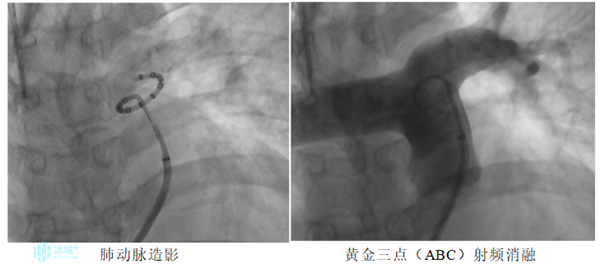

经过术前准备,哈医大一院心内科王召军教授对患者进行右心导管术检查(RHC),检查结果显示:平均肺动脉压(MPAP)为47mmHg,肺动脉楔压(PAWP)为23mmHg,明确诊断为左心疾病所致肺动脉高压,适合进行肺动脉去神经术(PADN)治疗。随后手术团队对患者主肺动脉末端与左肺动脉开口交接处的“黄金三点”解剖部位进行射频消融,术后即刻,平均肺动脉压(MPAP)降至42mmHg,肺动脉楔压(PAWP)降至19mmHg,手术顺利完成,全程仅耗时50分钟。